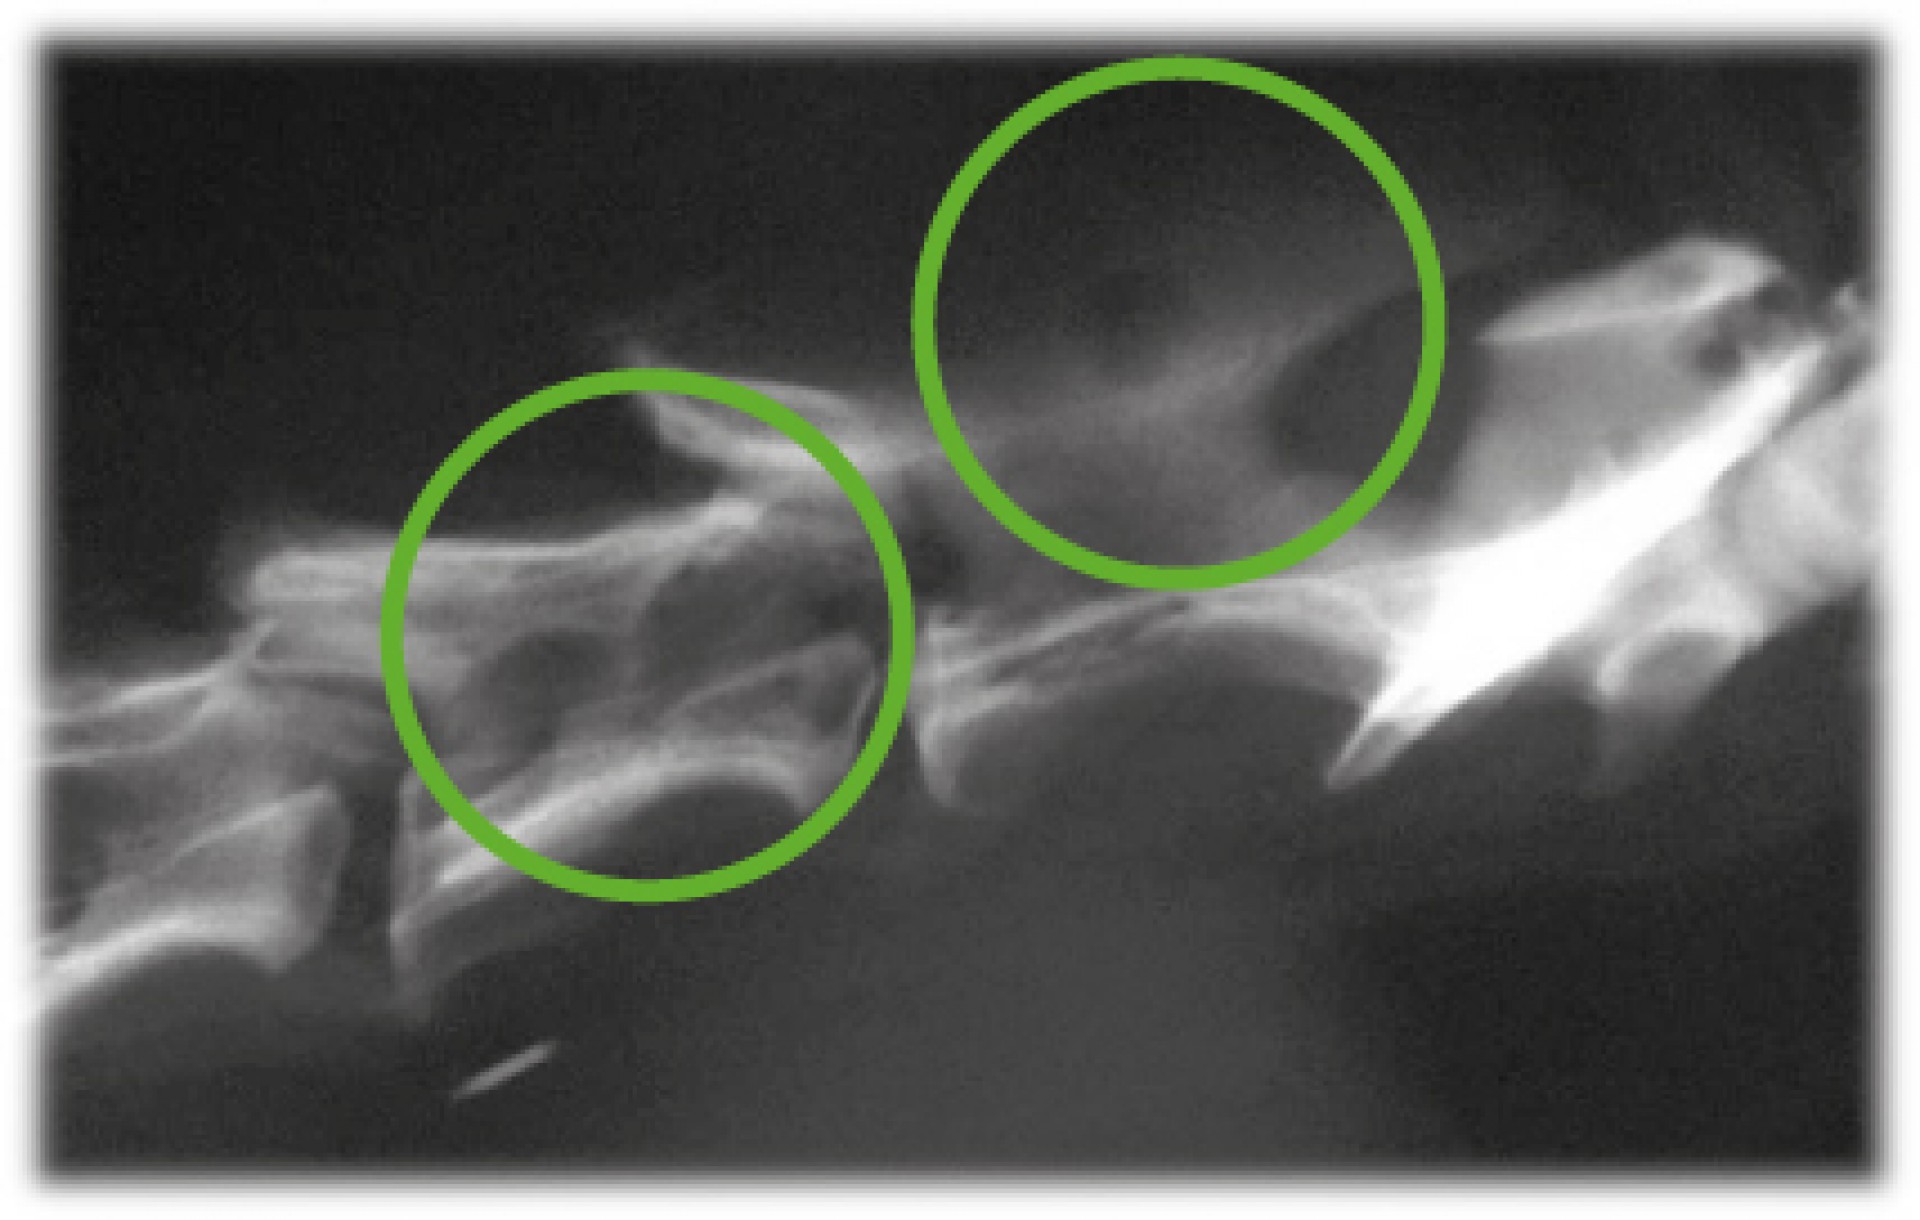

Míg az utóbbi esetben az elsődleges daganat eltávolítását, szövettani vizsgálatát követően az áttétes daganatok kemoterápiás/ sugárterápiás gyógykezelési lehetősége merül fel elsődlegesen, addig a primer gerincdaganatok kialakulása esetén annak pontos lokalizációját, a gerincoszlop alkotóelemeinek érintettségének maghatározását követően a daganat műtéti eltávolítására is sor kerülhet.A klinikai tünetek kialakulása sokféle lehet, szinte minden esetben egy folyamatosan rosszabbodó, idegrendszeri tünetek súlyosbodásával járó, gyakran azonos oldali mellső és hátsó végtagot érintő neurológiai kiesést tapasztalunk. A klinikai tünetek alapján azonban a gerinc daganatos megbetegedései nem különíthetőek el a hasonló kórlefolyású degeneratív megbetegedésektől (pl.: porckorongsérv). Így a diagnózis pontos felállításához kiegészítő vizsgálatokra mindenképpen szükség van. Ezek közé tartozik a natív röntgenvizsgálat, de mivel a gerincvelő környéki, a csontvázat nem érintő daganatok többnyire nem adnak röntgenárnyékot, ezért az egyszerű röntgen vizsgálaton túl egyéb képalkotó eljárásokra, kiegészítő vizsgálatokra is szükség lehet.

A háziállatok esetén a klinikai tünetek megjelenése a tulajdonosok számára sokszor olyan lassú folyamat, melyet szinte a mindennapok során észre sem vesznek. Az esetek döntő többségében már csak akkor jelentkeznek a szakellátást biztosító állatorvosnál, amikor már súlyos neurológiai tünetek alakulnak ki és a klinikai és kiegészítő vizsgálatok alapján a gyógyulás prognózisa kedvezőtlen. Míg a gerincvelő védelmét ellátó csontos váz, a gerinccsatorna fontos védelmi szerepe megkérdőjelezhetetlen, addig a daganatos megbetegedések esetén már viszonylag kis méretű tumorok keletkezésekor is markáns tünetek kialakulásához vezethet szilárdsága, hiszen a gerincvelő nem tud kitérni a növekvő daganat elől. Ez az oka annak, hogy olyan kisméretű tumorok esetében is számolhatunk klinikai tünetekkel, melyek a szervezetben sehol máshol nem okoznának problémát. A prognózist rontja az a tény is, hogy ezek a betegségek általában idült lefolyásúak (annak ellenére, hogy a tünetek sokszor hirtelen keletkeznek és gyorsan romlanak). Ezért fontos, hogy kedvencünkkel mindenképpen már az első tünetek jelentkezésekor keressük fel kezelő állatorvosunkat!